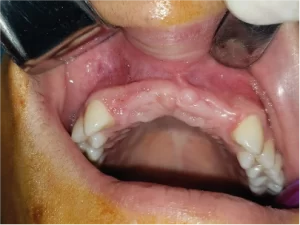

Caso de agenesia de incisivos laterales, fresado con guía quirúrgica